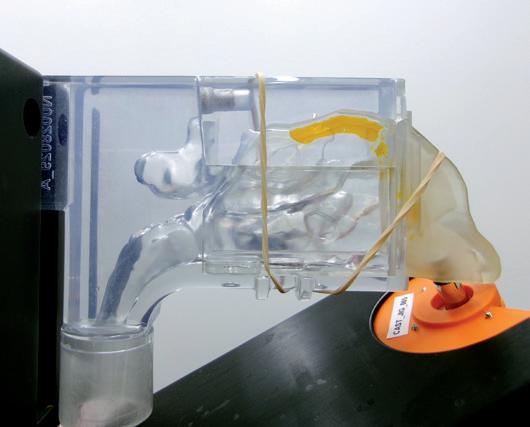

Interview – Exploring Nasal Casts in Nasal Drug Development

Julie Suman, Vice-President, Scientific Affairs

Aptar Pharma